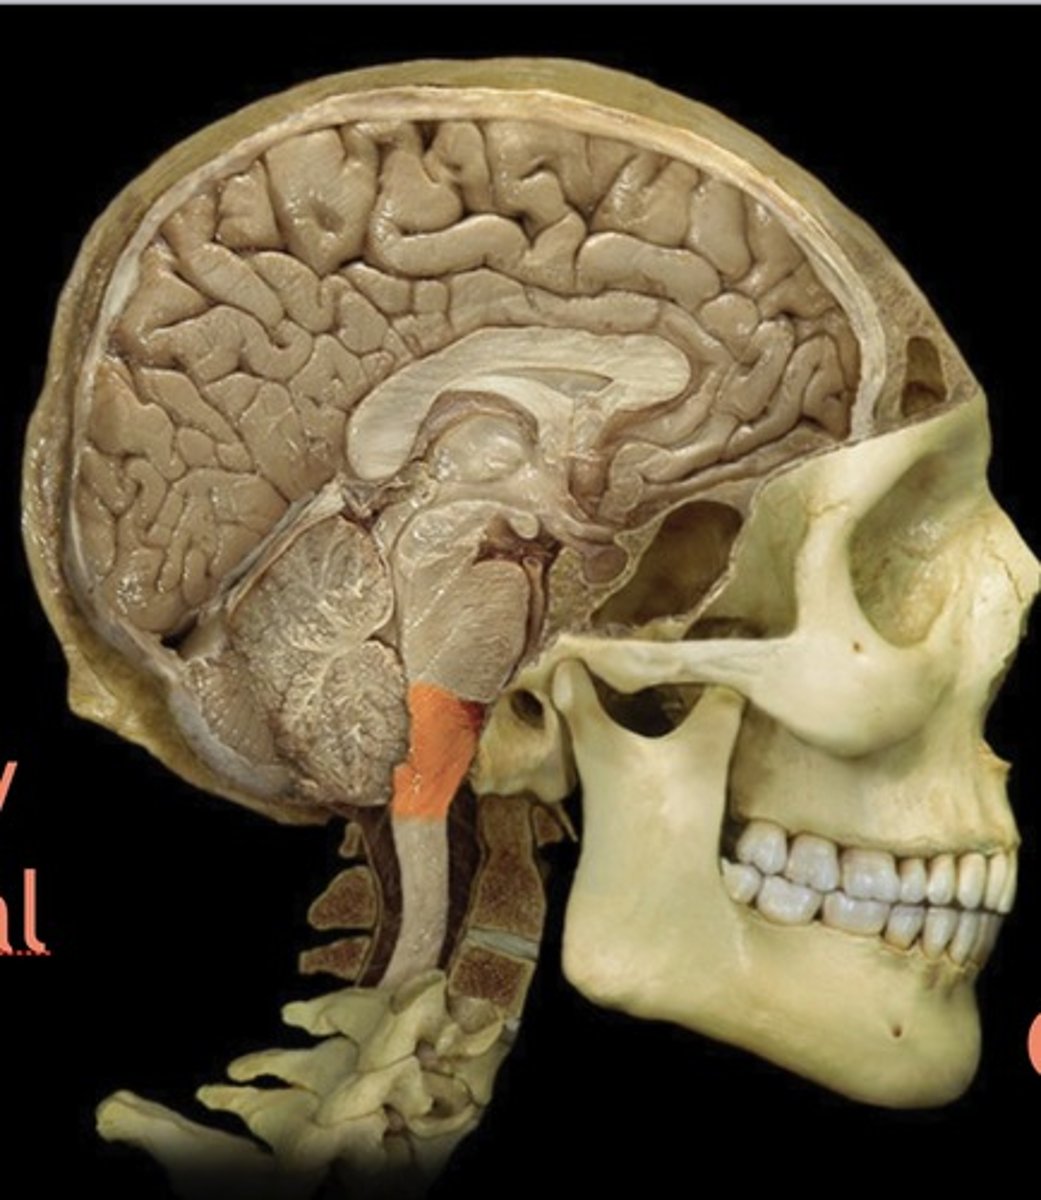

brainstem

Name this structure

Midbrain

Name this structure

Pons

Name this structure

Medulla Oblongata

Name this structure

Cervical Spinal Cord